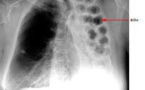

Le Sénégal à l’instar de la Communauté Internationale célèbre la journée mondiale de lutte contre la Tuberculose ce Mardi 24 mars 2014 à Kaffrine. Le thème retenu est: « Atteindre les manquants ». L’objectif est de contribuer à l’atteinte l’objectif global des trois millions au niveau mondial. Neuf (9) millions de personnes par...